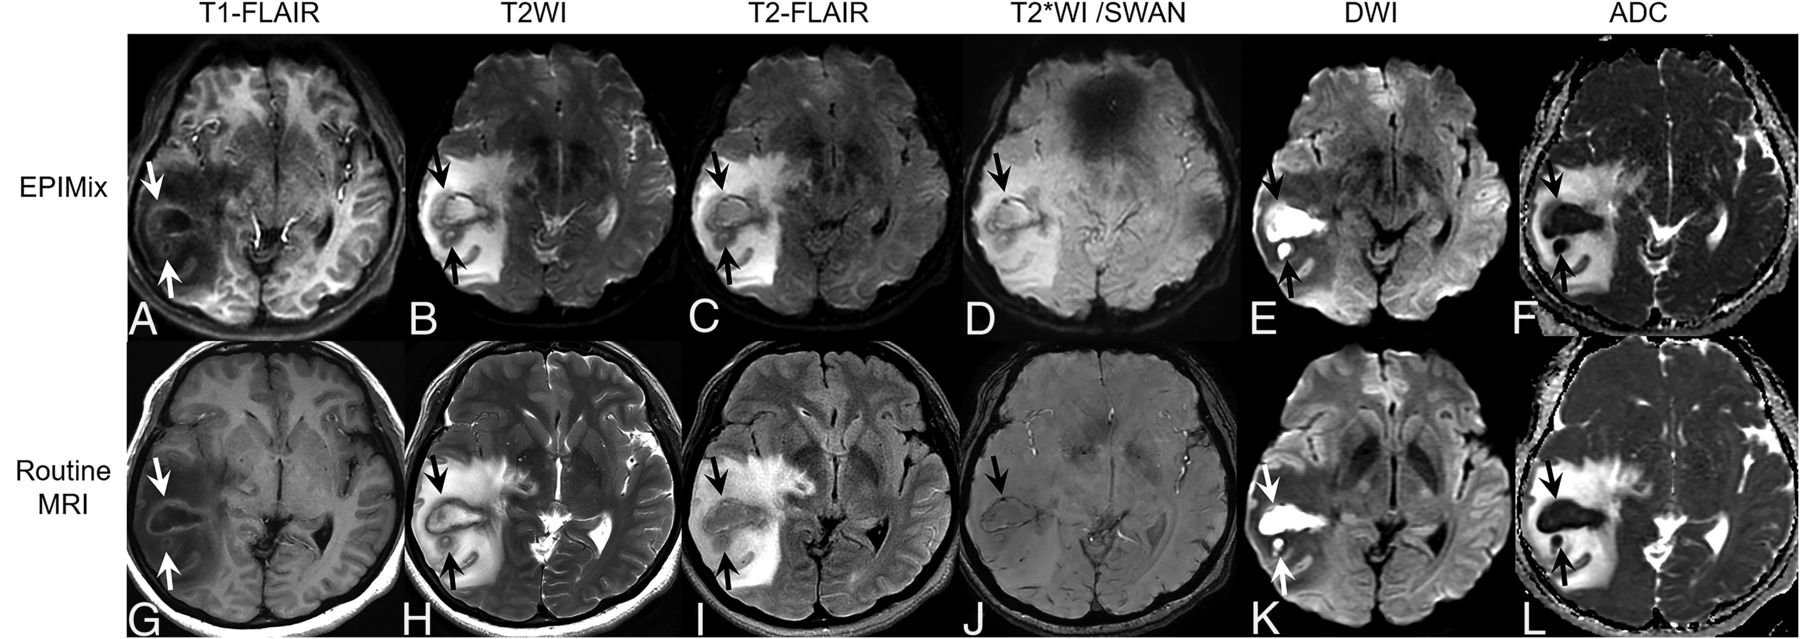

A 48-year-old woman with brain abscesses. There are 2 irregularly shaped masslike lesions with perilesional edema in the right temporal lobe. The internal content shows hypointensity on T1-FLAIR (A and G) and hyperintensity on T2WI (B and H) and T2-FLAIR (C and I) (arrows). The internal content shows diffusion restriction on DWI (E and K) (arrows). There are blooming artifacts on T2*WI (D) and SWAN (J) (arrows). These findings are well-visualized on both EPIMix MR imaging (A–F) and routine MR imaging (G–L).